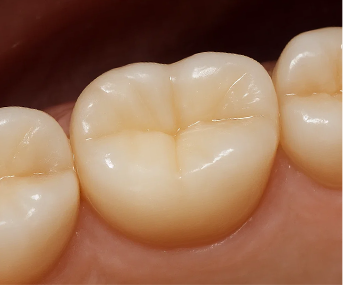

왜 지르코니아 크라운을 많이 선택할까

지르코니아는

자연치에 가까운 색감과

강한 내구성을 동시에 가진 재료입니다.

앞니처럼 웃을 때 보이는 부위에서는

색이 어둡거나 금속 느낌이 나지 않아야 하고,

어금니처럼 힘을 많이 쓰는 부위에서는

단단하게 오래 버텨줘야 합니다.

지르코니아는 이 두 가지를

비교적 균형 있게 만족시키기 때문에

앞니·어금니 구분 없이

많이 선택되는 크라운 재료입니다.